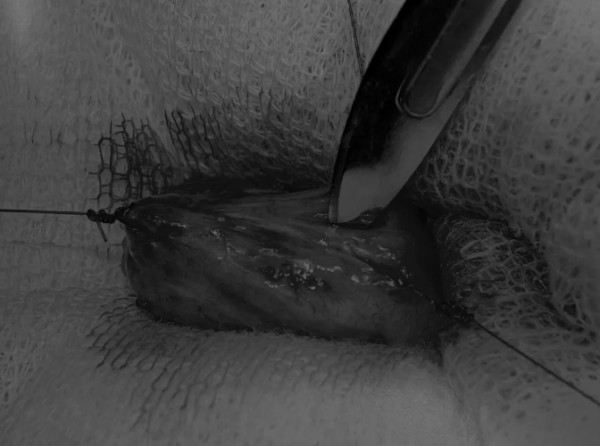

在中线开腹手术后,确定膀胱,将其取出并隔离(图1)。为了使膀胱持续暴露,可在膀胱中线两侧各放置一根固定缝线(图2)。

图1 将膀胱从腹腔中取出,用无菌外科敷料隔离。为了防止膀胱滑入腹部,可在膀胱顶部放置一根固定缝线,由助手通过止血钳夹住固定缝线做持续牵引

在牵引缝线之间选择血管扩张较差的区域用手术刀切开膀胱壁(图3)。在牵引缝合线之间用手术刀在血管不良的区域做切口。切开膀胱壁后,膀胱内的手术可按手术方案实施,例如取出结石(图4)。

图3 避开主要的膀胱血管,做一个尽可能小的切口